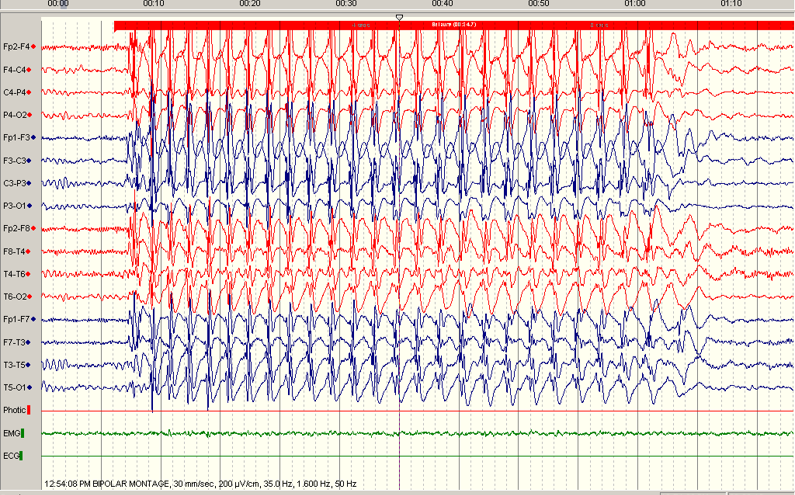

Question: An 8-year-old boy presents with frequent staring episodes while in class. Based on the electroencephalogram (EEG) shown, which of the following is the most appropriate medication for this patient?

Explaination: The EEG demonstrates the typical 3-Hz spike and wave pattern seen in absence epilepsy. The best medication for absence epilepsy is ethosuximide<br>Valproic acid is also used in absence epilepsy, but typically if there are generalized tonic-clonic seizures in addition to staring episodes. Phenytoin and carbamazepine have the potential to worsen generalized epilepsy.